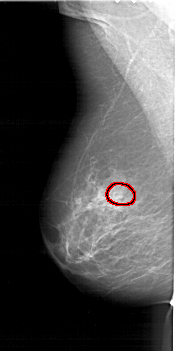

FILE: A_1415_1.LEFT_CC.OVERLAY

TOTAL_ABNORMALITIES 1

ABNORMALITY 1

LESION_TYPE CALCIFICATION TYPE PLEOMORPHIC DISTRIBUTION CLUSTERED

ASSESSMENT 4

SUBTLETY 3

PATHOLOGY MALIGNANT

TOTAL_OUTLINES 1

BOUNDARY